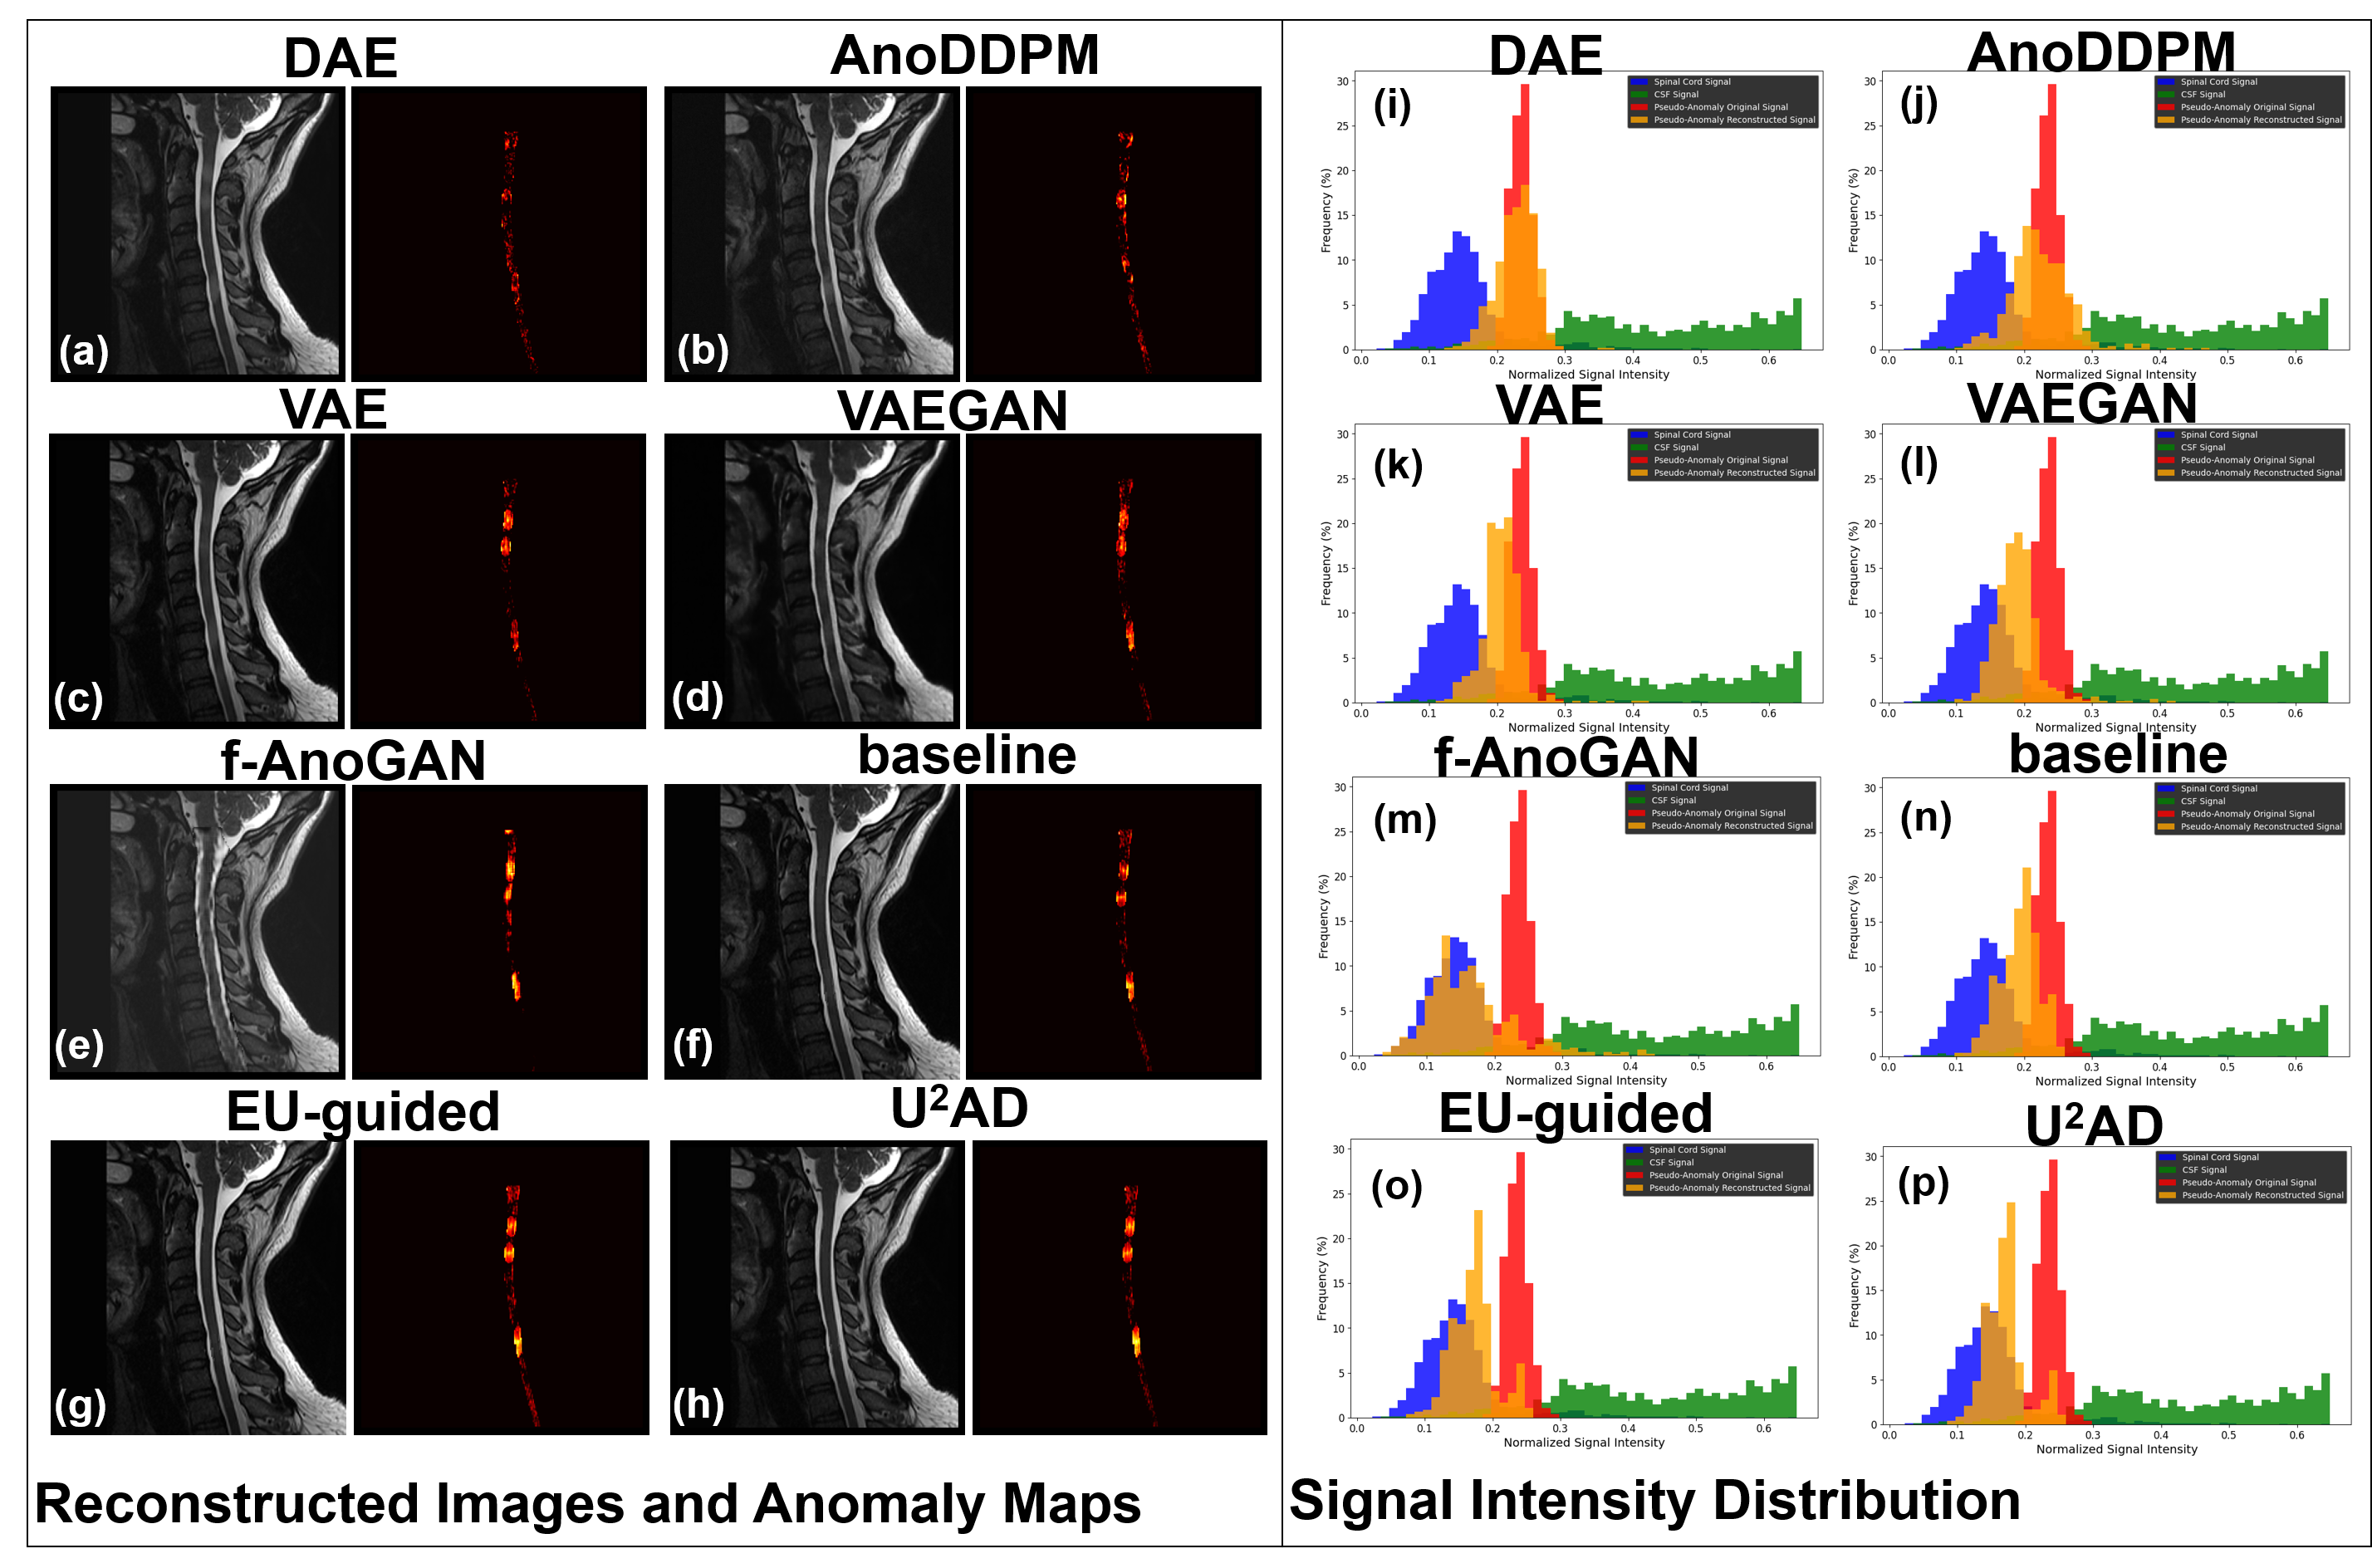

Figure 6 illustrates the signal intensity distributions of reconstructed pseudo-anomaly regions in the OpenNeuro T2w dataset. Specifically, the signal distribution of pseudo-anomaly regions in reconstructed images (orange) is compared against the normal SC signal (blue) and the pseudo-anomaly signal (red) from the original images. The goal of a UAD model is to reconstruct normal signals while highlighting the reconstruction error in pseudo-anomaly regions, such that the reconstructed pseudo-anomaly signals align closely with the normal SC signal and deviate from the original anomaly signal. For a fair comparison, all models were trained using Strategy 3 on the dataset. The results reveal that DAE and AnoDDPM fail to effectively capture the normal SC signal. In contrast, VAE and VAEGAN exhibit reconstructed distributions that fall between normal and anomaly signals. f-AnoGAN and achieve distributions closer to the normal SC regions, with demonstrating a shape highly similar to the normal signal distribution. However, the distribution of f-AnoGAN exhibits deviations at both ends, exceeding the normal signal range, which could introduce noise in anomaly maps. Further examples illustrating this issue are provided in the A.2.

A.2 Reconstruction analysis on pseudo-anomalies

Using the example illustrated in Figure A1, we analyze the reconstruction performance of various UAD models specifically on pseudo-anomalous regions. To ensure a fair comparison, all models are trained following dataset training Strategy 3. The reconstruction results are shown in Figure A2. Among the tested models, DAE and AnoDDPM exhibit overfitting, as evident from their reconstructed results and signal distributions. VAE and VAEGAN demonstrate partial differentiation between normal SC signals and anomaly signals; however, the separation is not as pronounced as in f-AnoGAN and the proposed framework. f-AnoGAN achieves the closest reconstructed signal distribution to the normal SC signal, as shown in (m). However, its reconstructed image (e) appears blurry, potentially introducing noise into the anomaly maps and leading to misdiagnoses. In comparison, the proposed framework outperforms the baseline models. As shown in (h), achieves better reconstruction quality and anomaly detection performance. Its reconstructed pseudo-anomaly regions retain the signal intensity characteristics of normal SC regions, with anomaly maps effectively highlighting abnormal areas.